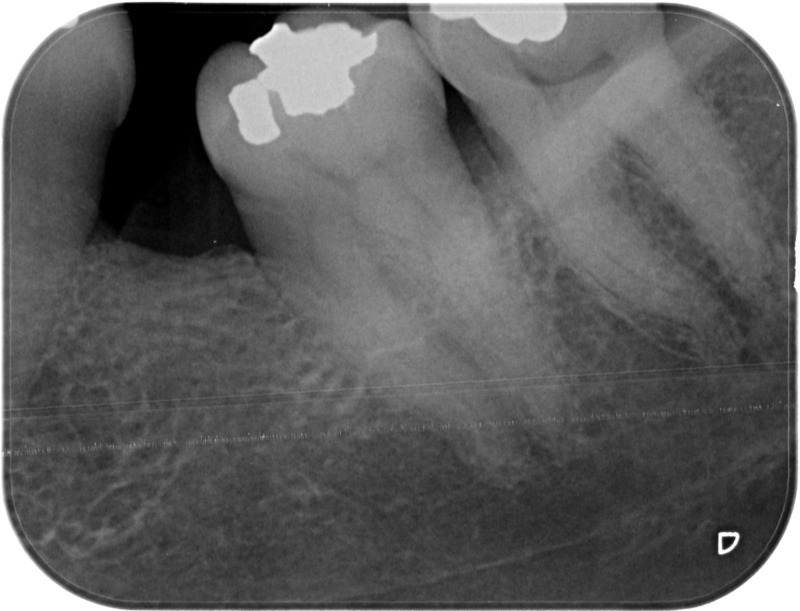

• Reprise de traitement endodontique : La manœuvre consiste à retourner à l’intérieur des racines d’une dent déjà traitée. Il arrive occasionnellement qu’une nouvelle inflammation se déclare suite à une reprise de carie ou une fracture de la dent, ou si le premier traitement endodontique est incomplet. Après s’être assuré que la dent lésée était conservable, il convient de désinfecter de nouveau le réseau canalaire parfois très complexe. La nouvelle obturation des canaux devra être protégée aussi rapidement que possible pour éviter une éventuelle contamination bactérienne.

Avant

Après